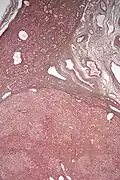

Inflammatory hepatocellular adenoma

Inflammatory hepatocellular adenoma